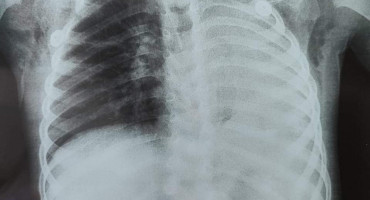

Un paciente ingresó al Instituto Nacional de Enfermedades Respiratorias y del Ambiente “Prof. Dr. Juan Max Boettner” (Ineram) para realizarse unos estudios tras accidente de motocicleta y en las radiografías fue hallado un anillo de oro en su pulmón.